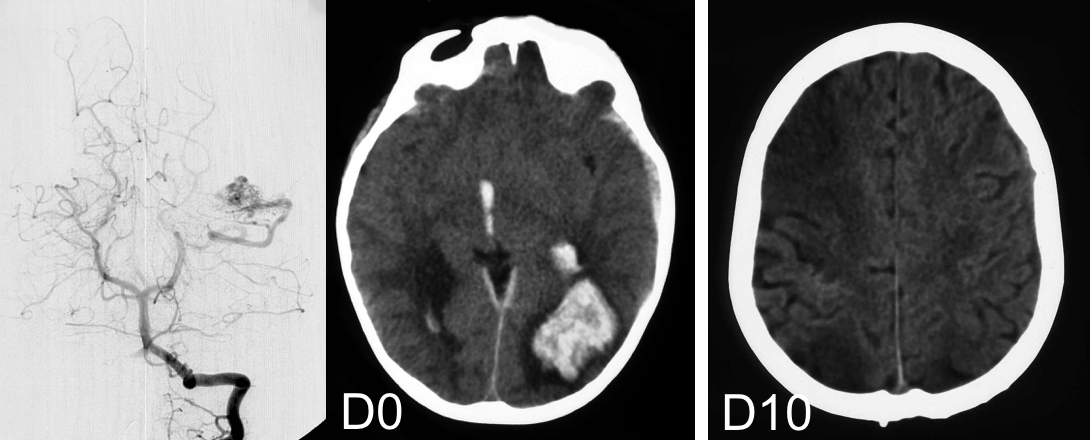

le saignement peut être favorisé par un effort physique, mais la majorité survient sans cause particulière voire pendant le sommeil. le risque de resaignement est estimé à environ 10% dans l’année qui suit. les MAV les plus agressives, celles qui tuent le plus, sont situées dans le cervelet.

la majorité des MAV de l’enfant se révèlent en effet par une rupture hémorragique, qui survient « comme un coup de tonnerre dans un ciel serein », avec céphalées, vomissements, déficit et troubles de conscience progressifs, parfois signes d’engagement. dans notre série, 78% des patients se présentaient avec une MAV rompue, 43% étaient comateux

- vasospasme

classiquement lié à l’hémorragie méningée anévrysmale, le vasospasme peut également survenir après hémorragie cérébrale par rupture de MAV ; il semble néanmoins obéir à des mécanismes particuliers comme le montre sa topographie souvent inattendue. le traitement par inhibiteur calcique, qui n’a pas d’AMM chez l’enfant ni en dehors de la rupture anévrysmale, peut être malgré tout nécessaire.

le resaignement

il survient rarement dans les jours qui suivent l’hémorragie ; il représente cependant une menace tant que la MAV n’est pas totalement éradiquée